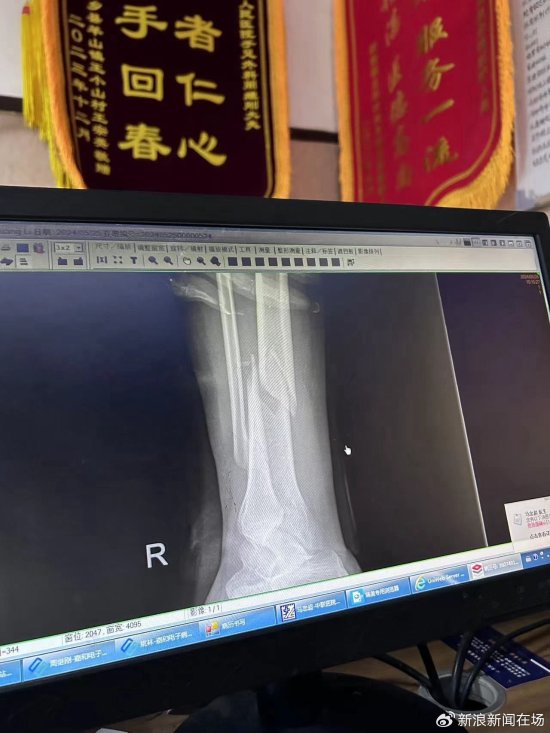

到了医院之后发现是骨折,医生建议做手术打钢钉,但小董认为自己还年轻,不想动刀,决定进行保守治疗。医院医生说上一期节目也有人骨折。